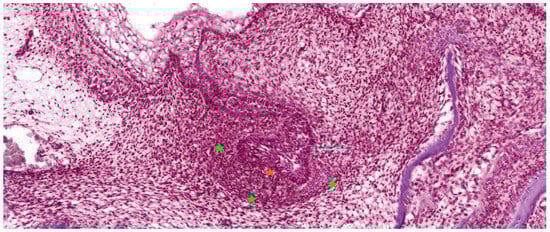

4.2. Degeneration of Hertwig’s Root Sheath

4.3. Formation of the Periodontal Ligament